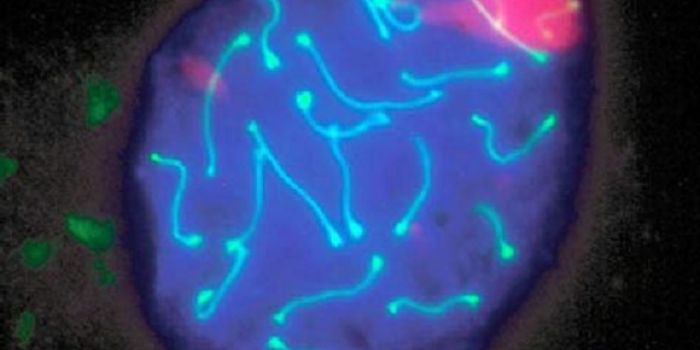

JUL 15, 2015Genetics & GenomicsThe role of telomeres in the aging process has become a hot topic in biology, and recent study have linked telomeres - t ...

FEB 21, 2023Cell & Molecular BiologyThe Griffith Lab at UNC discovered telomeric protein & potential biomarker VR (green), shown in the nuclei (blue) of hum ...

MAY 20, 2021Genetics & GenomicsWhile the vast majority of our genes are in the genome that's held in the nuclei of cells, mitochondria are also known t ...